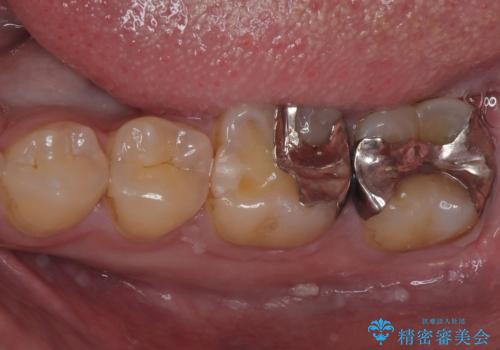

銀歯を外したい オールセラミッククラウン

担当医 有澤哲郎